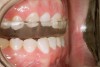

Figure 4   Indentations on tongue caused by forceful pressing of tongue on lingual surfaces. By pushing the tongue anteriorly, the airway is opened.

Figure 4